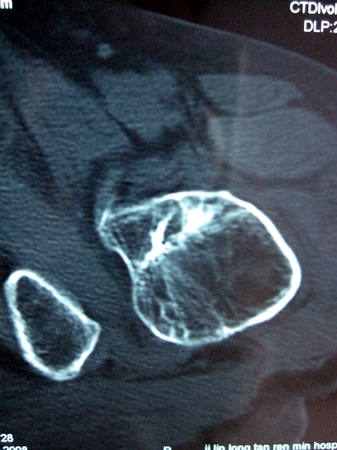

以下是引用lkc8963在2008-12-19 21:19:00的发言:[br]左?右?患侧大转子上移,股骨颈骨质浓杂,髋周见多发条片状骨化影,以小转子为著,多为陈旧性股骨颈骨折后改变并骨化性肌炎.请咨询既往史!